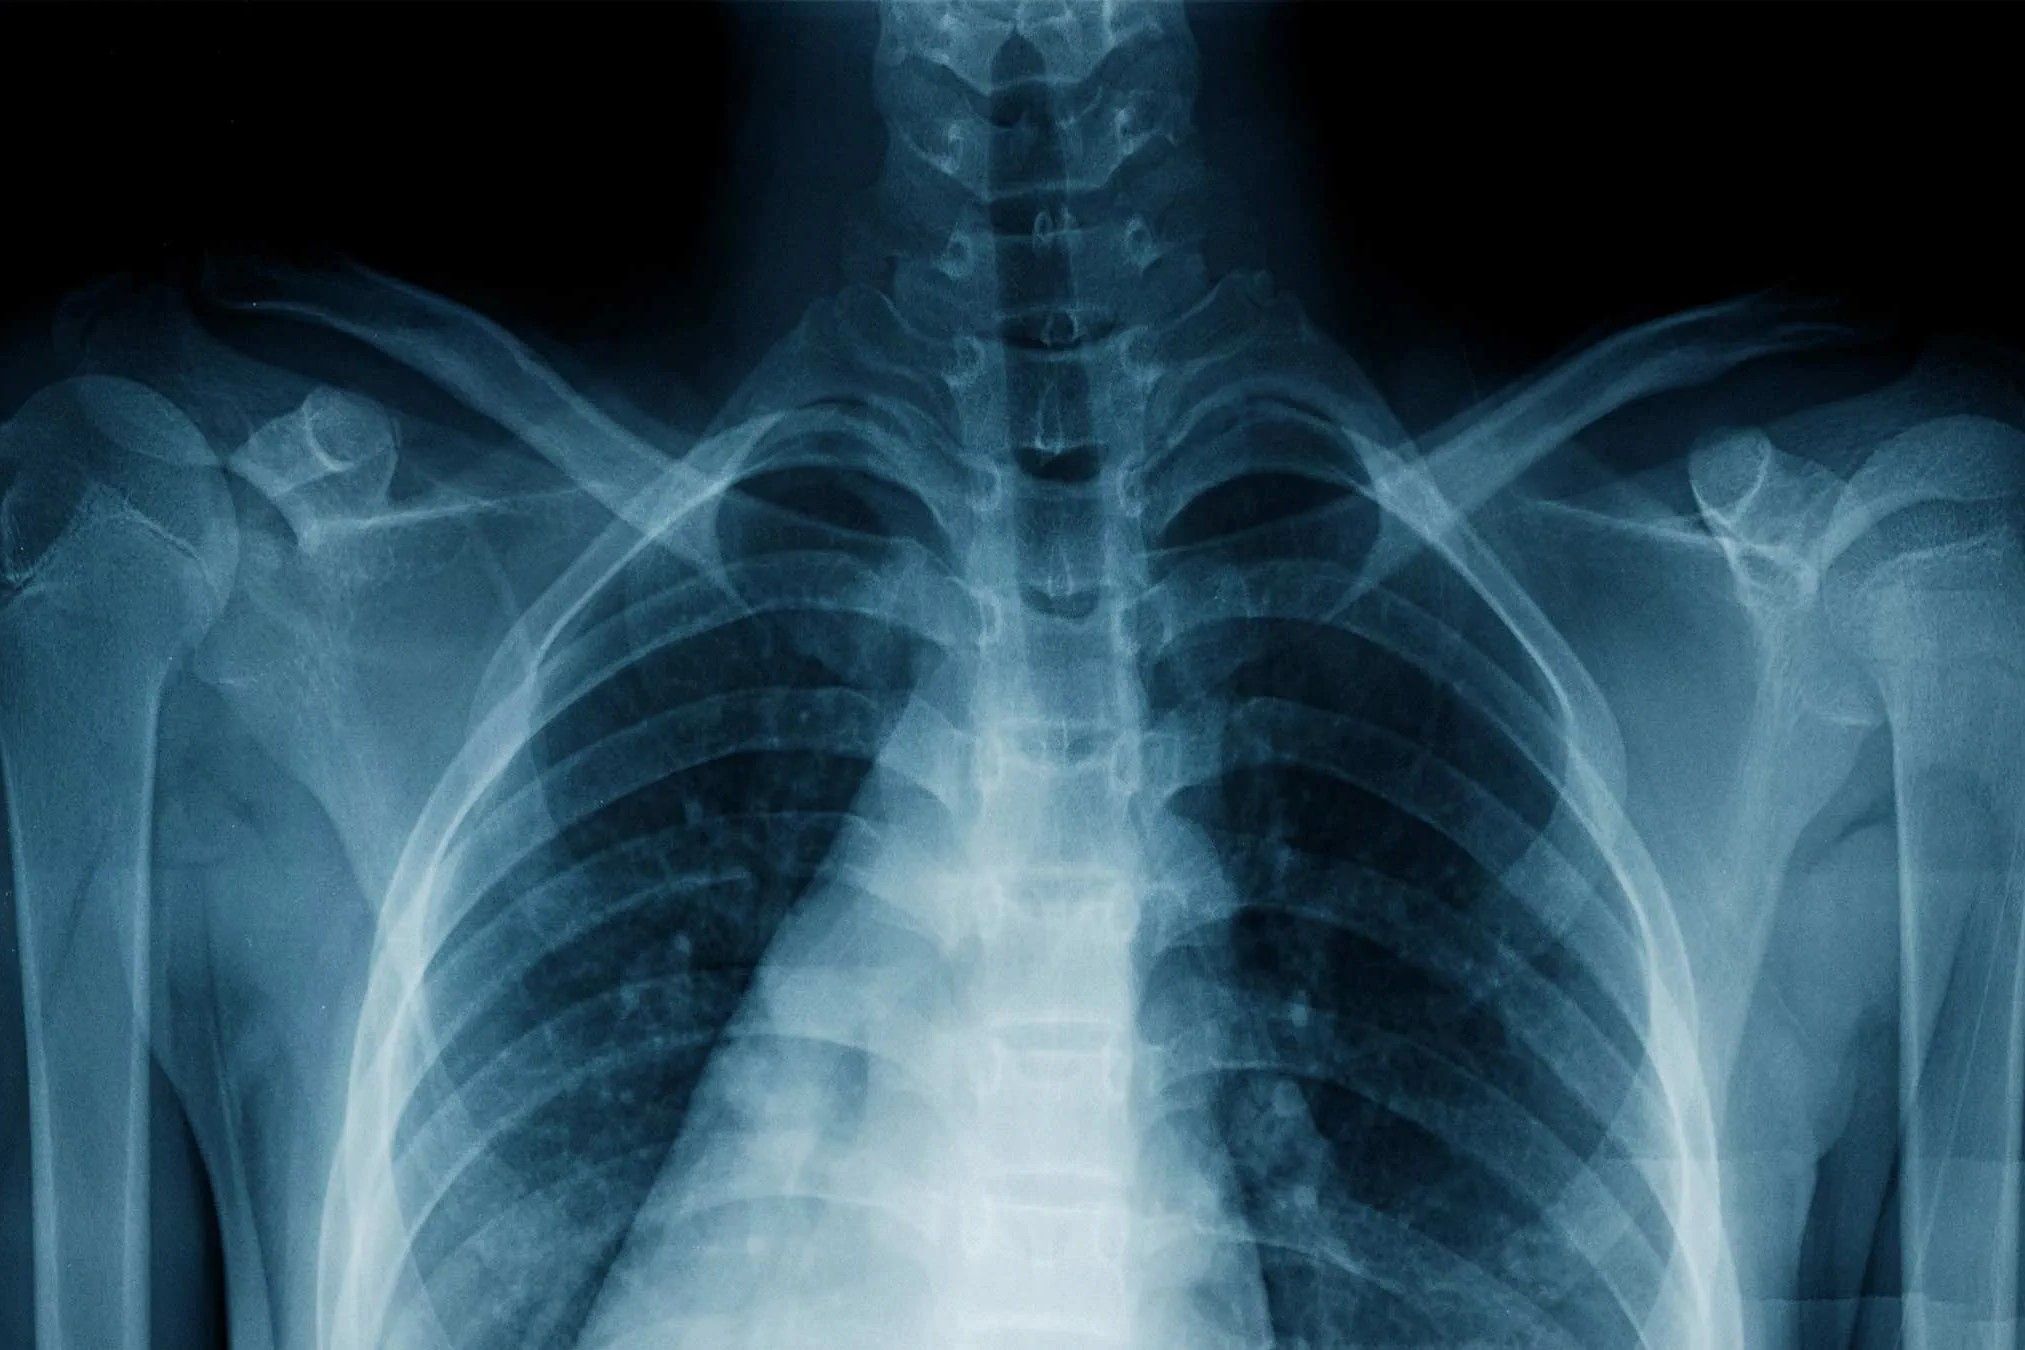

X-ray imaging is a fascinating technology that allows us to see inside the human body without making a single cut. It has revolutionized medicine and continues to be a crucial tool in diagnosing and treating various conditions. Here are some intriguing facts about X-ray imaging.

Understanding how X-rays work can help appreciate their significance. The process involves generating X-rays and capturing their interaction with the body on a detector.

- When X-rays pass through the body, they are absorbed by dense materials like bones, creating a contrast on the image.

- Soft tissues absorb fewer X-rays, appearing darker on the X-ray film or digital detector.

- The resulting image is called a radiograph, which radiologists interpret to diagnose conditions.

- Conventional radiography is the most common type, used for imaging bones and chest.